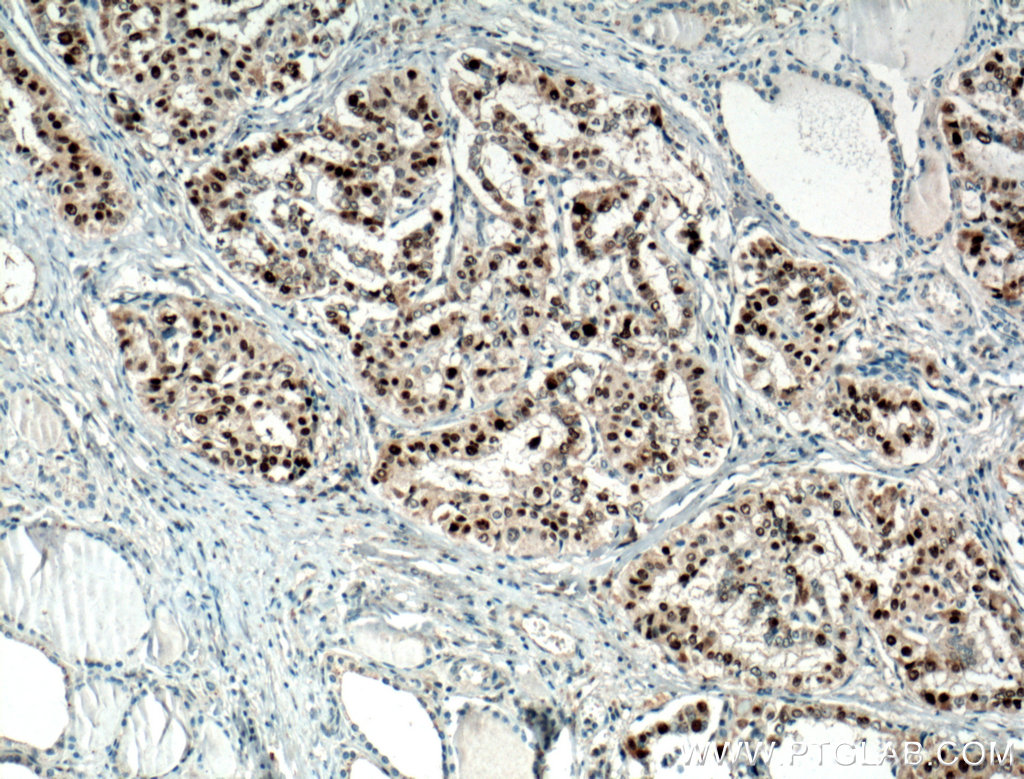

| Positive IHC detected in | human colon cancer tissue, human breast cancer tissue, human cervical cancer tissue, human kidney tissue, human stomach cancer tissue, human thyroid cancer tissue Note: suggested antigen retrieval with TE buffer pH 9.0; (*) Alternatively, antigen retrieval may be performed with citrate buffer pH 6.0 |

| Immunohistochemistry (IHC) | IHC : 1:5000-1:20000 |